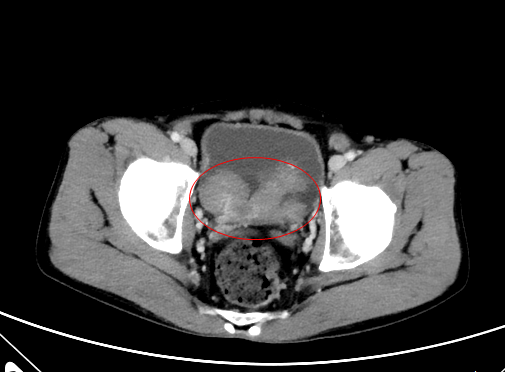

罗大哥便找到泌尿外科主任顿金庚教授处问诊,顿金庚教授知晓罗大哥情况后,便要他做了腹部彩超、CT,检查结果提示:膀胱内有肿块阴影。进一步经泌尿系CT、膀胱镜及病检,诊断为:膀胱肿瘤。

罗大哥立马住进了泌尿外科病房进行治疗。顿金庚教授高度关注罗大哥的病情,特地组织全科医生进行案列分析及讨论后一致认为:考虑患者膀胱占位性病变,考虑为膀胱恶性肿瘤,且肿瘤面积较大,不能切除彻底,且容易穿孔导致肿瘤播散,唯有行根治术。顿金庚教授团队讨论后建议为患者施行全膀胱切除+回肠代膀胱术。